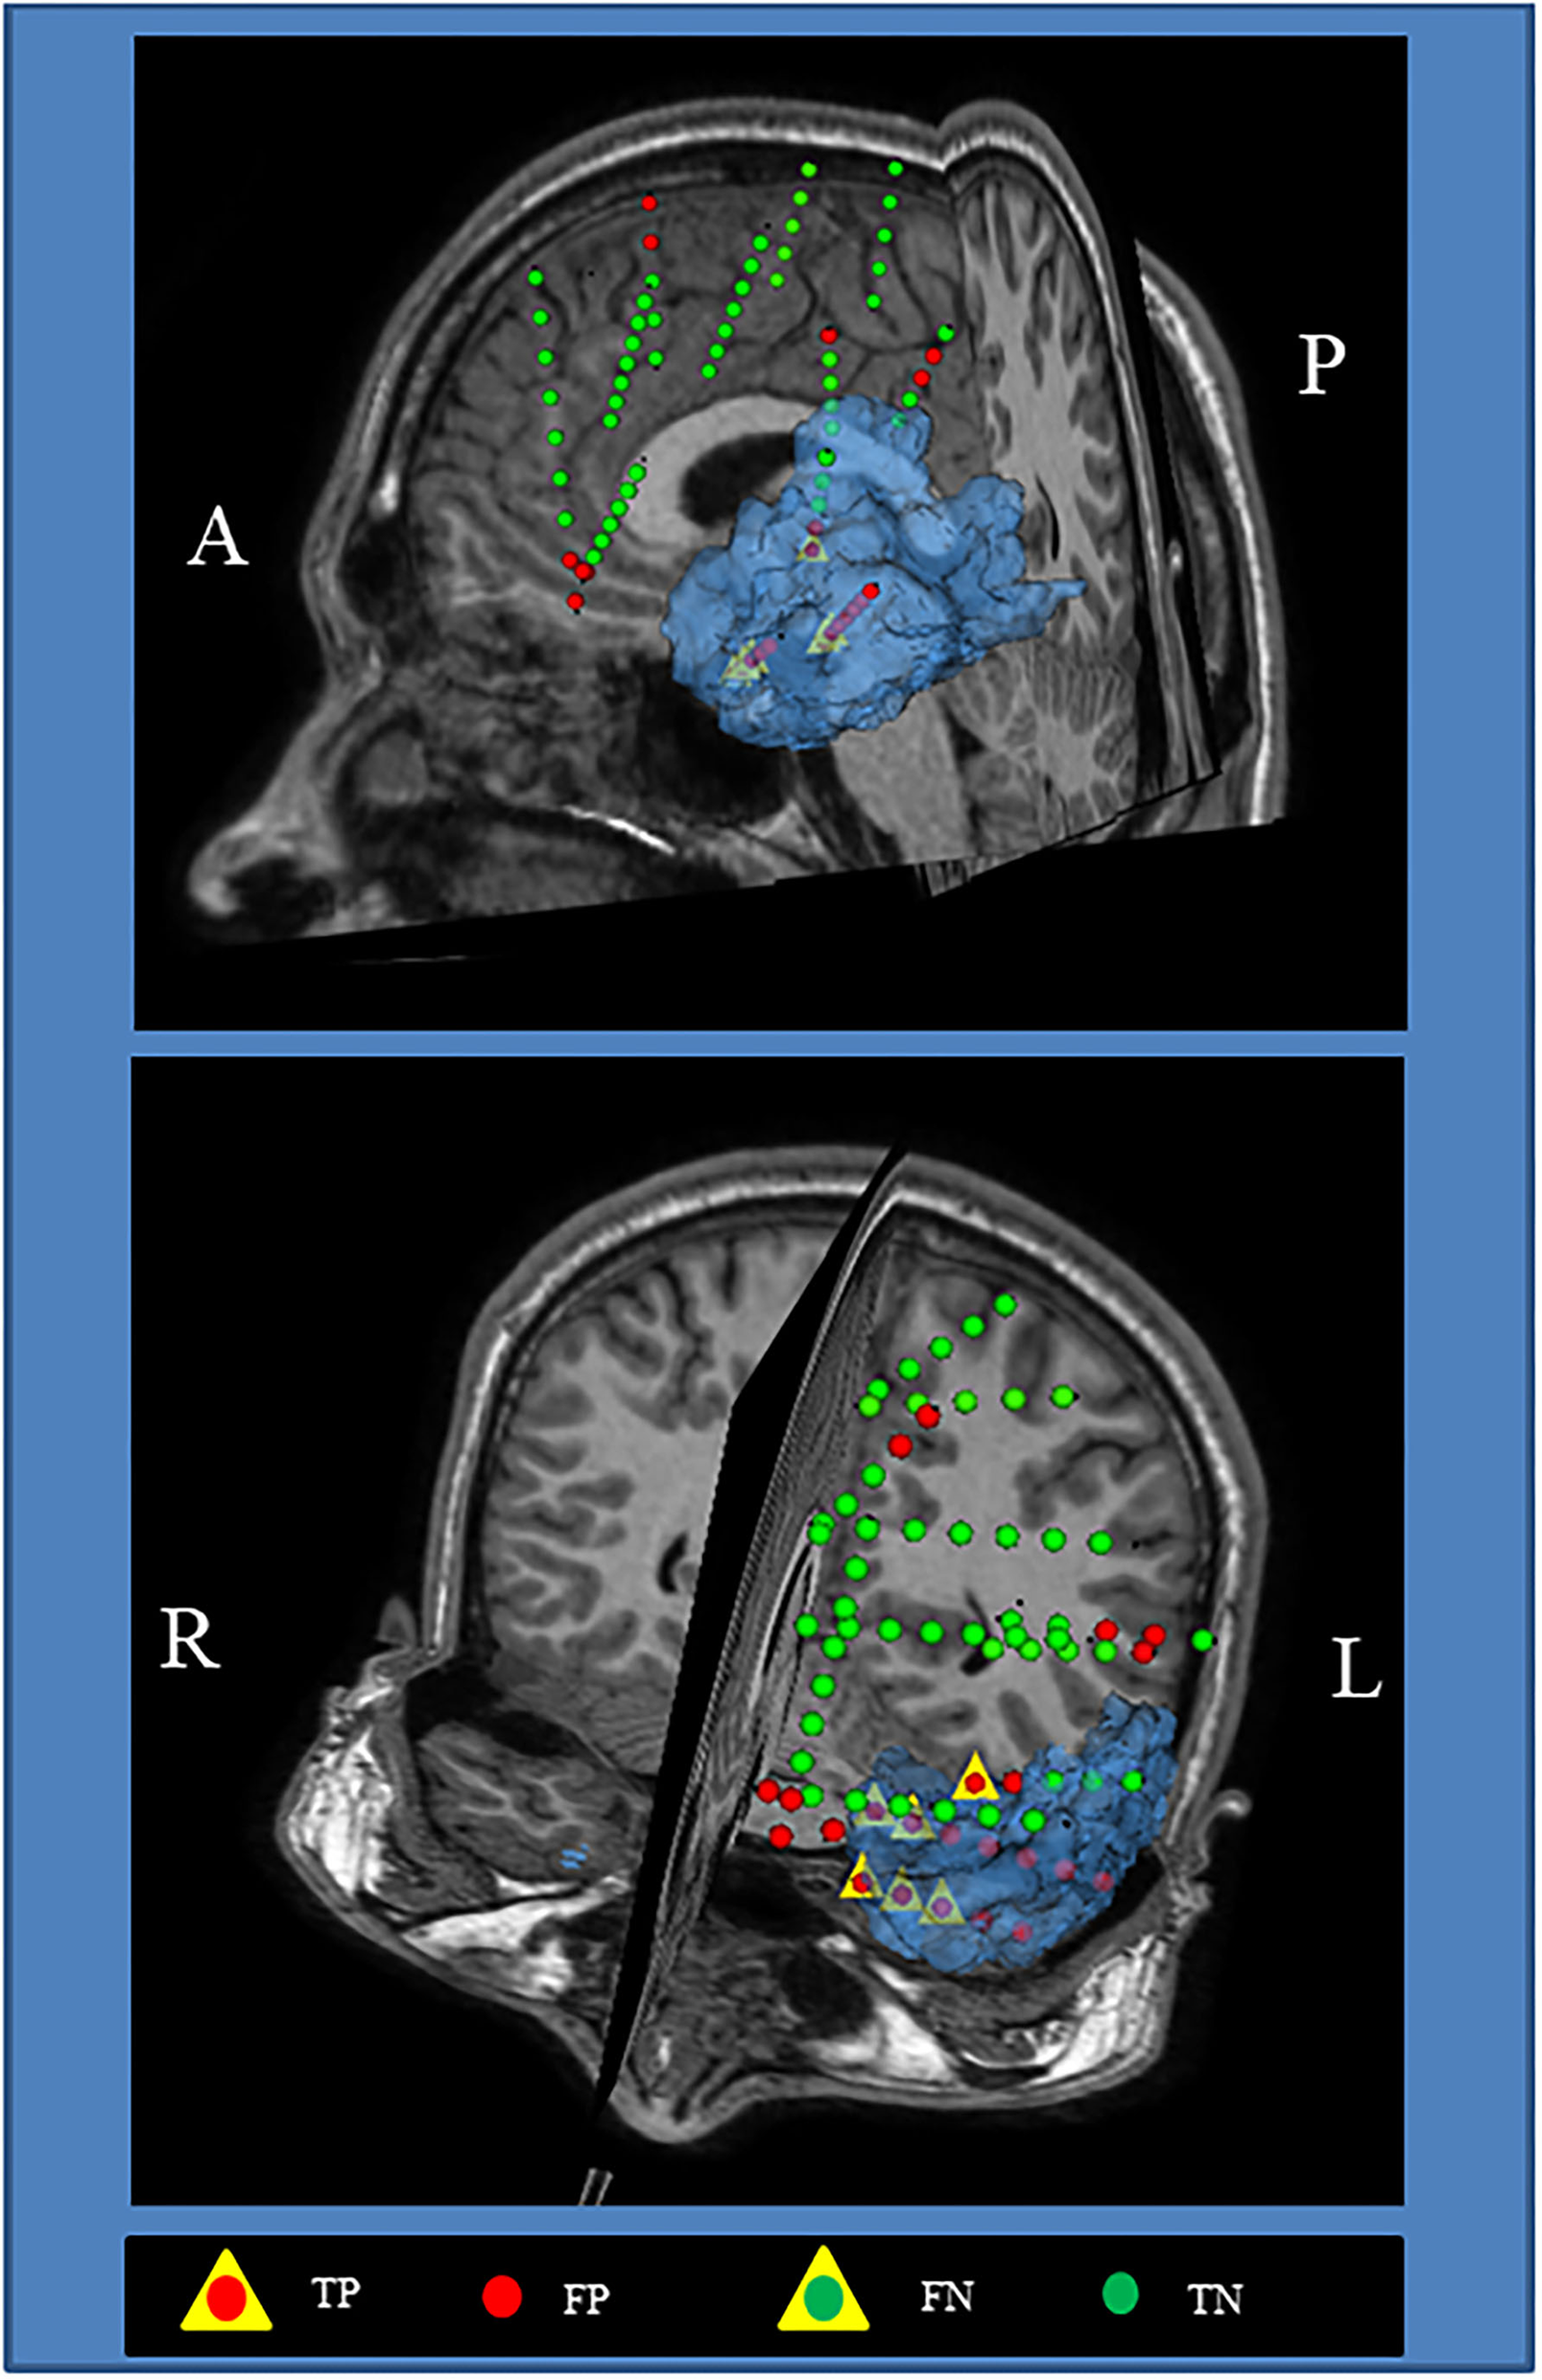

Figure 7 shows the visualization of the surgical 3D scene for a representative patient (pt2), such as an indication of the resected zone (blue area), true EZ and non-EZ leads, and the EZ and non-EZ classification provided by the RUS + EnsDA method.

Visualization of the surgical 3D scene for a representative patient (pt2). The Blue area indicates the final resected zone. Red and green dot points indicate leads classified as epileptogenic zone (EZ) A, anterior; L, left; P, posterior; R, right.